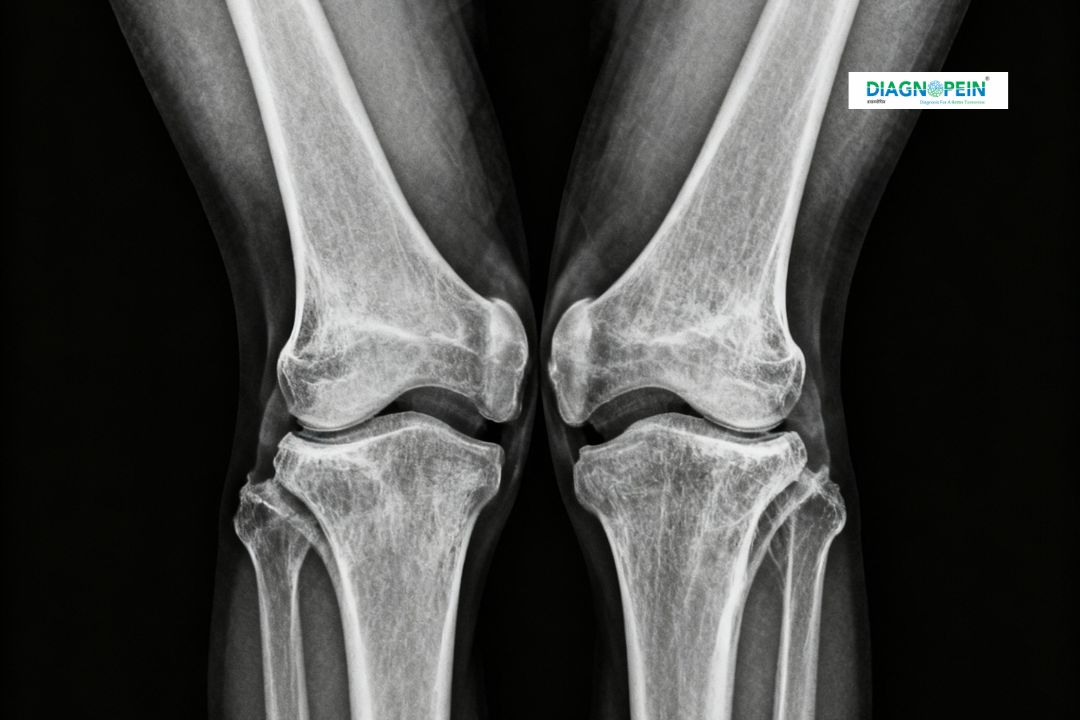

An X-ray Both Knee Varus View is a specialized diagnostic imaging test that captures both knees in a slight inward angulation position (varus). This view helps radiologists and orthopedic specialists assess joint alignment, bone structure, cartilage spacing, and overall knee condition. Diagnopein in Karad offers high-quality digital X-ray services that ensure accurate imaging results for effective diagnosis and treatment planning.

X-rays are widely used to evaluate bone and joint health. The Varus View of both knees provides a clear comparison of both joints under load-bearing conditions to identify issues like osteoarthritis, ligament injuries, deformities, and bone density loss.

Knee pain and stiffness are common among adults and elderly individuals. The X-ray Both Knee Varus View plays a crucial role in identifying underlying causes that might not be visible in a regular front (AP) or side (lateral) X-ray image. At Diagnopein, Karad, our advanced imaging technology ensures every detail is captured precisely, allowing doctors to observe cartilage wear, joint alignment, and structural changes caused by arthritis or chronic injury.